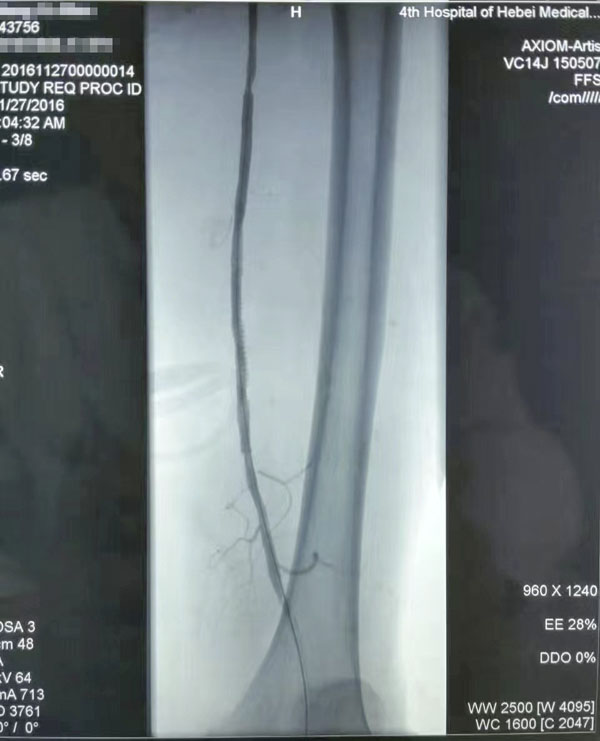

介入治療前后對比

糖尿病足重在預防,而預防和治療下肢血管病變是防治糖尿病足的有效措施。下肢血運重建是糖尿病下肢血管病變治療的根本,采用球囊擴張開通狹窄或閉塞的下肢動脈(介入治療),恢復直達足部的血流,是治療糖尿病下肢血管病變的根本措施,具有立竿見影的效果。這也是近年來在糖尿病足診治方面取得的又一新進展,為廣大糖尿病下肢血管病變患者解除了痛苦,使糖尿病足患者截肢率由34%降至4%。世界防治糖尿病日到來之際,希望廣大糖尿病患者關注糖尿病下肢血管病變,保護自己的雙足,做到早發現、早治療,提升幸福感,快樂每一天。